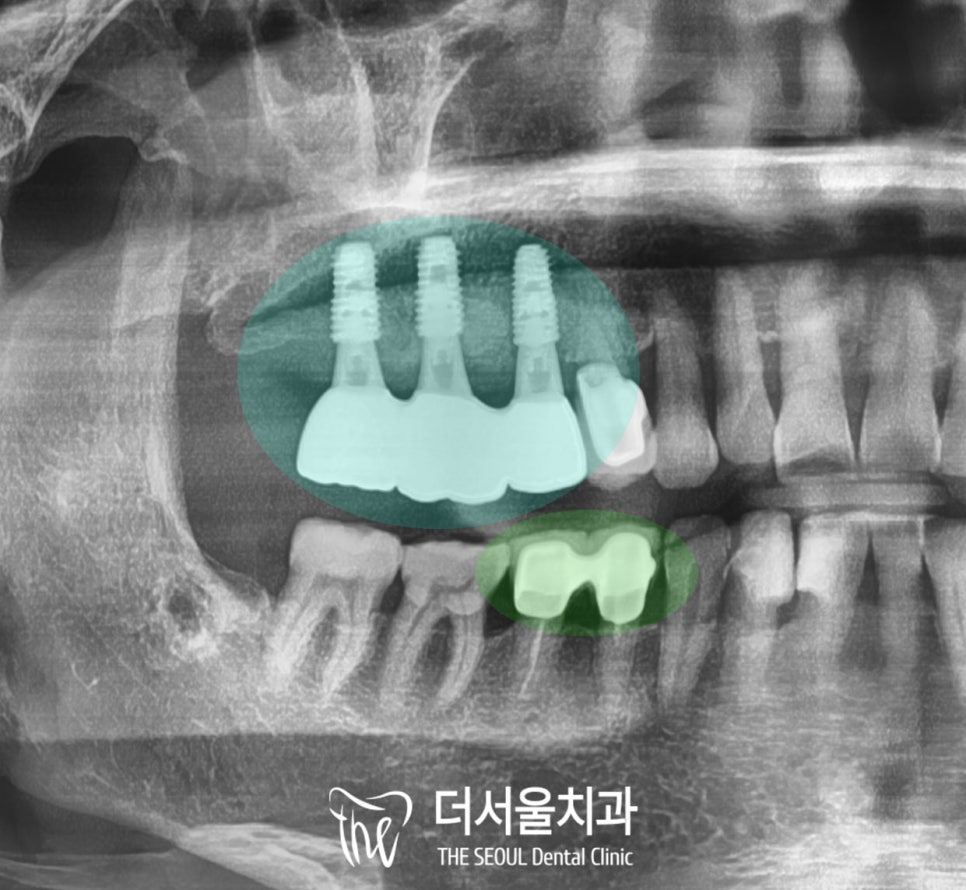

그러고 나서 우리가 원하는 위치에

잘 식립되었는지 확인하면

당일 수술은 모두 끝이 납니다.

그동안 다량의 골이식을 해둔

오른쪽 위 구치부의 픽스처는

제가 생각한 것보다 훨씬 더 단단하게

잘 융합이 되었고,

감염이나 문제없이

회복이 잘 되었기에

이제는 보철만 올려드리면 되겠습니다.

이때는 맞물리는 대합치도

크라운이 조금 깨져있어서

동시에 교체해 드렸습니다.

구치부 교합에 맞추어

위아래 동시 수복까지

완료한 모습인데요,

인공치근을 구강 내로 연결하는 지대주와

크라운 모두 개인 맞춤형으로 제작하였기에

본인에게 딱 맞는 보철이

잘 올라간 것을 확인할 수 있습니다.

또한 보철의 종류는

내구성과 심미성이 뛰어난

지르코니아를 사용하여

외국에서도 잘 사용하실 수 있도록

도와드렸습니다.